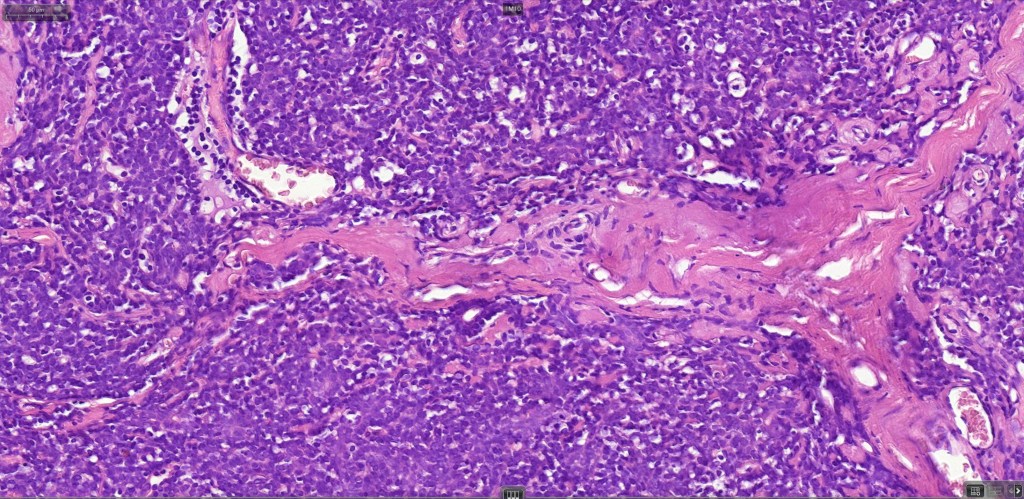

Histological features

•Nodule/multiple blue encapsulated nodules in the dermis +/- subcutaneous fat

•Common association with an adjacent nerve & exceptional intraneural component

•Outer layer of small intensely basophilic cells surrounding larger pale staining or eosinophilic cells with vesicular nuclei & small nucleoli

•Intra-tumoral lymphocytes

•Ductal & exceptionally, glandular differentiation

•No pleomorphism & only sparse mitoses or no mitoses

•Basement membrane thickening & intralobular eosinophilic globules